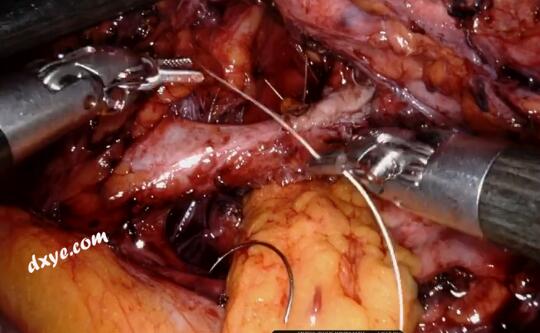

2.jpg

识别肾盂